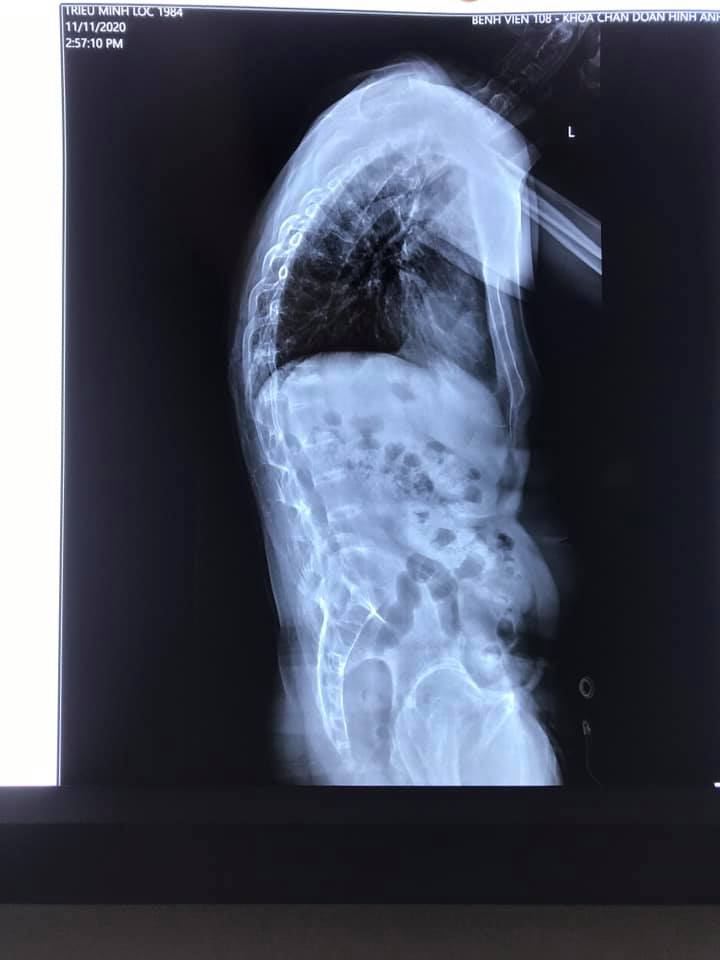

Đau cột sống, đau nhức xương khớp là tình trạng mà rất nhiều người ở mọi độ tuổi đang gặp phải và luôn đặt cho nó một sự quan tâm nhất định. Tùy vào từng cấp độ bệnh lý khác nhau các cơn đau cũng sẽ có những mức độ biểu hiện khác nhau. Nhưng chung quy lại vẫn khiến chúng ta cảm thấy bị đau đớn, khó chịu.

Chính vì thế, theo bác sĩ chấn thương chỉnh hình Trần Trung Kiên có thể chỉ là một cơn đau nhỏ nhưng STRESS sẽ một phần tác động thêm gây ra những cơn co cơ, chèn ép thần kinh mạch máu, gây giảm đi lượng lưu thông máu đến các hệ cơ xương khớp…. Dẫn đến việc bạn suy nghĩ bản thân ĐAU là do đang bị một chứng bệnh nào đấy vô cùng nặng. Khi não bộ càng tập trung sự chú ý vào CƠN ĐAU sẽ gây ra biến đổi của thần kinh trung ương khiến triệu chứng ĐAU ngày càng nghiêm trọng hơn. Một vòng lẩn quẩn cứ liên tục tiếp diễn sẽ khiến người bệnh bị nhấn chìm trong những suy nghĩ tiêu cực, những cơn đau dai dẳng không lối thoát và dẫn đến những hậu quả không mong muốn.